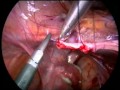

Ureteric Stricture Laparoscopic Repair